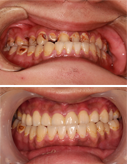

“牙缝大”不开心-瓷贴面7天让你美丽无忧

15岁小帅哥全口虫牙 根管修复露笑颜

不要等牙疼时才想起保护

龋齿不可大意 牙髓炎太可怕

治疗牙周病 还得早着手

只想变美 那就现在

健康爱美的大门前没有“男士止步”

收拾小龅牙 最正确的决定

小小种植牙 托起大梦想

种牙种健康 最美夕阳红